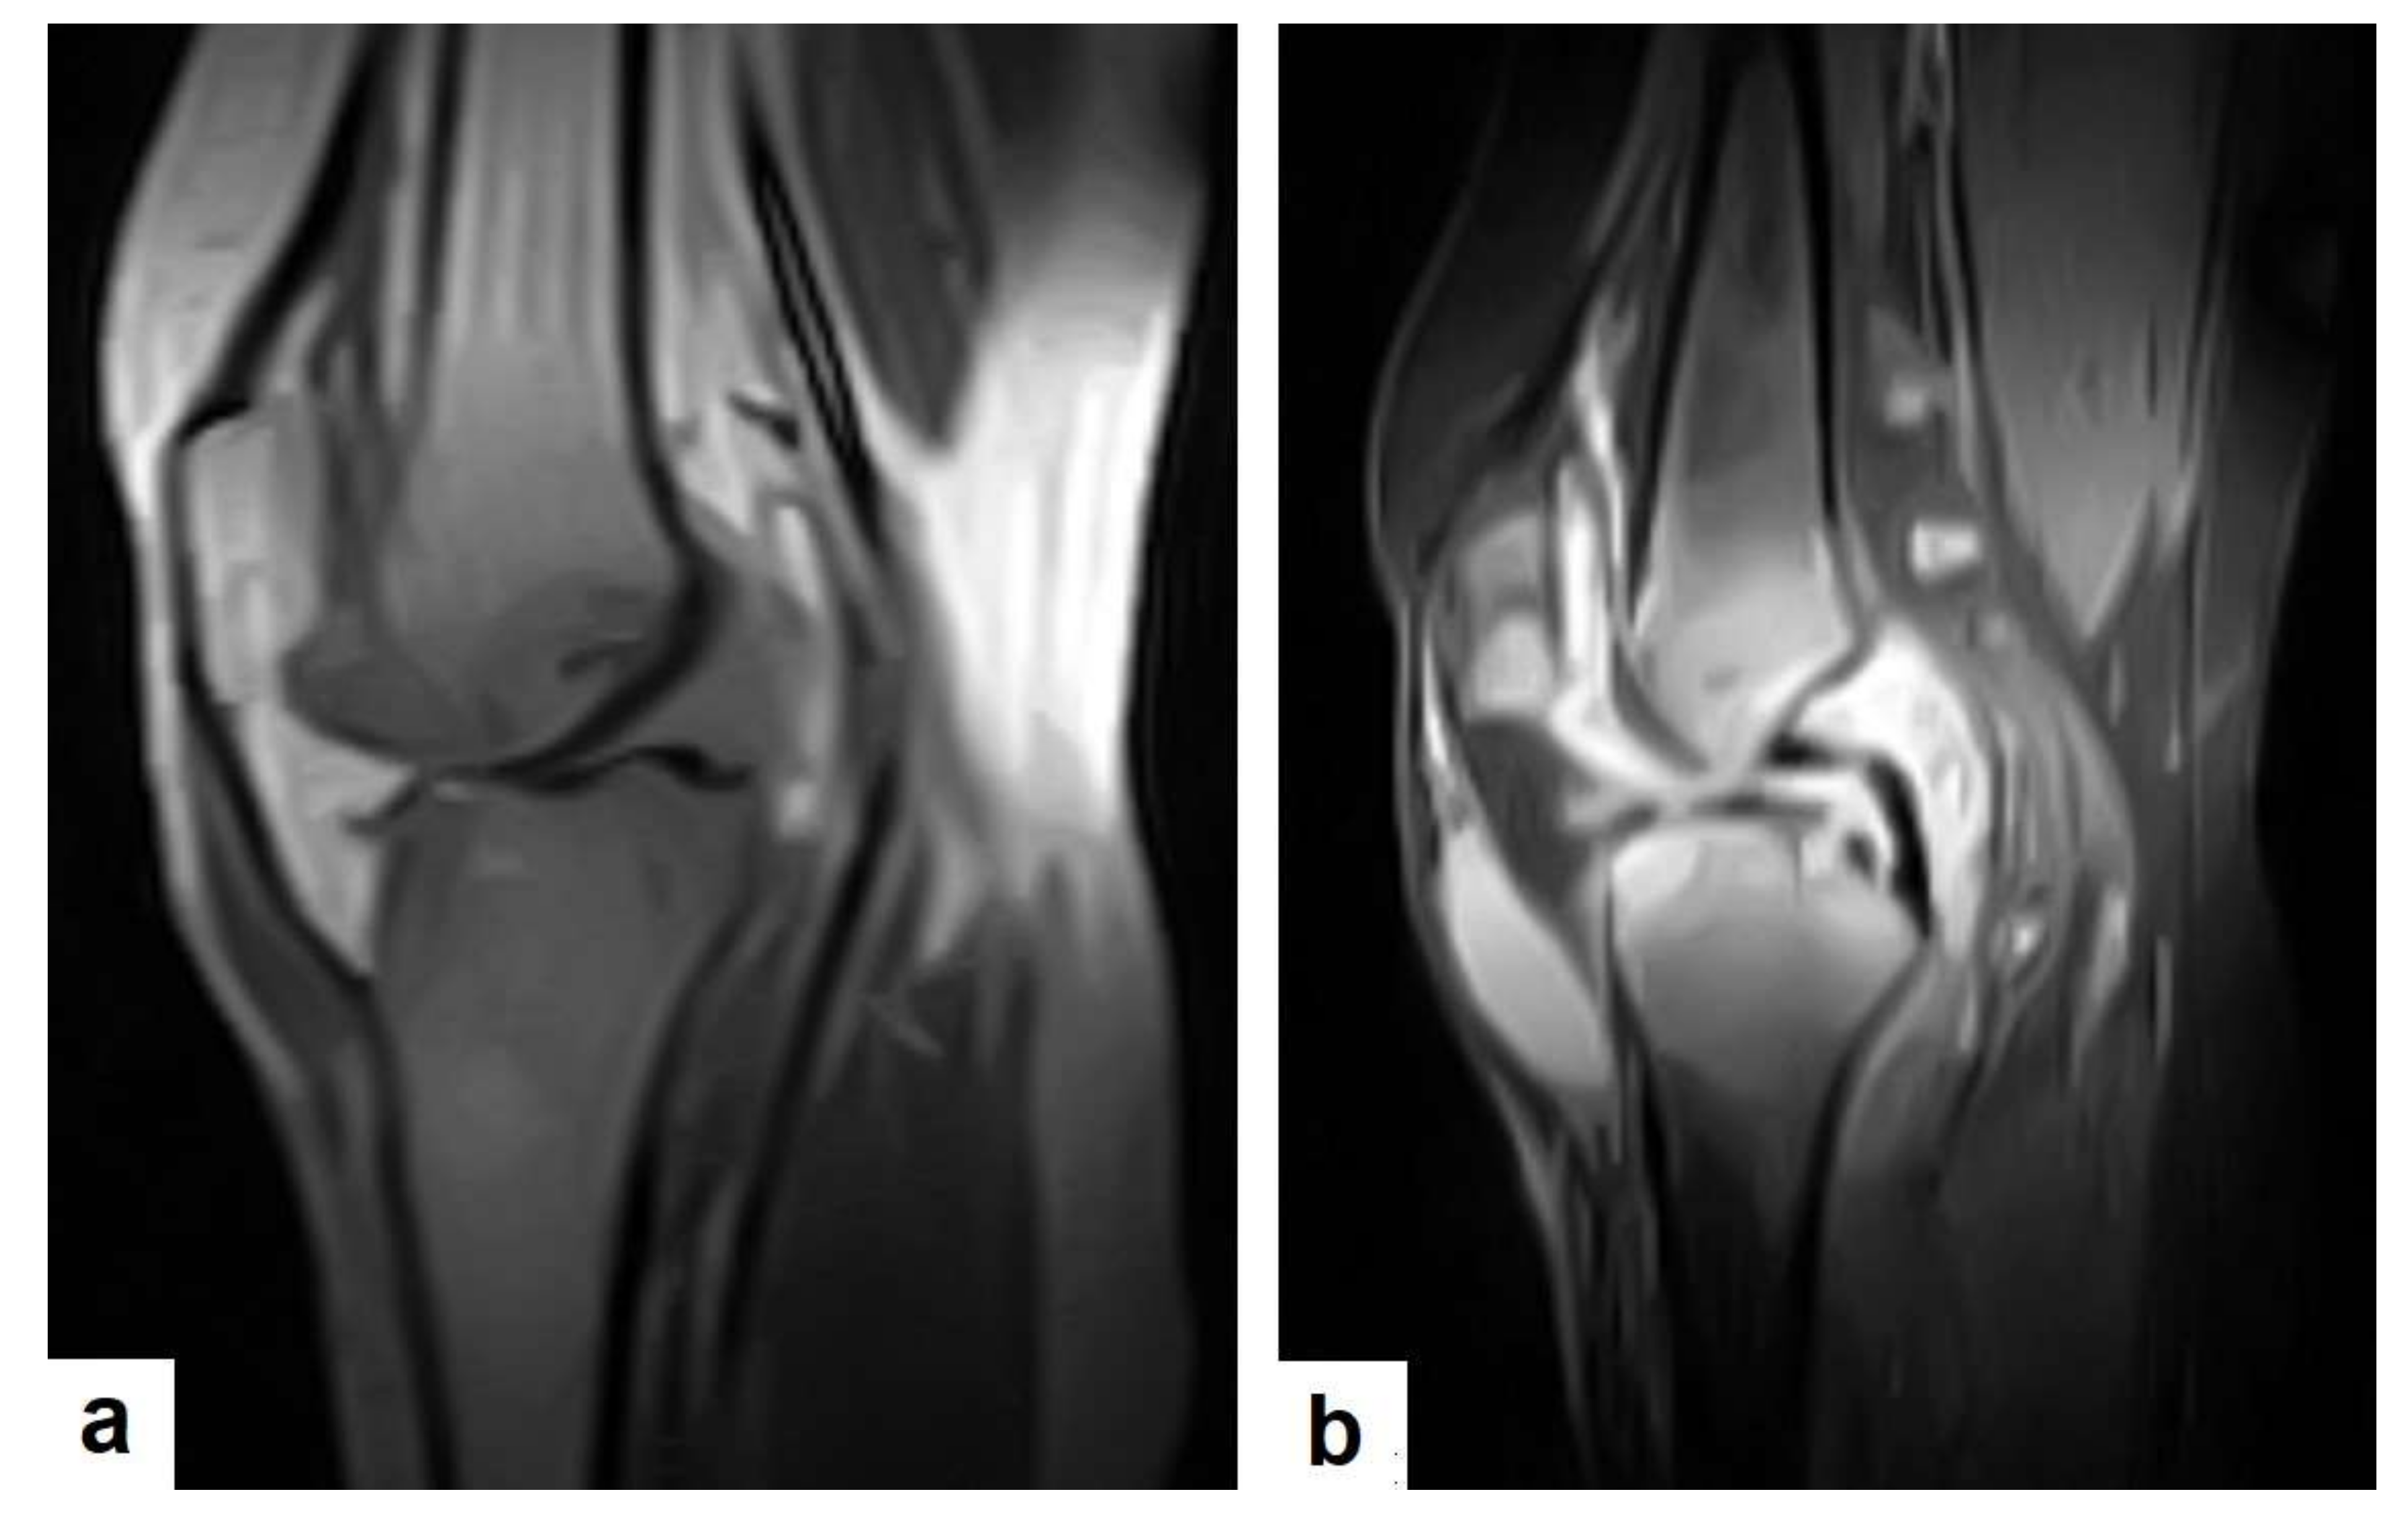

TB can affect any part of the musculoskeletal (MSK) system, and symptoms of TB may be insidious, causing TB not to be considered. CT and MRI imaging modalities can bring suspicion to TB diagnoses [57]. MSK TB has a wide range of radiological features that can mimic many pathologies all over the body. However, radiological assessment is often the first step in the diagnosis of MSK TB [58]. The most common type of MSK TB is tuberculous spondylodiscitis (Potts disease), which accounts for 50% of MSK TB [57,58] (Figure 18 and Figure 19). Osteoarthritis TB affects joints or bones. It usually affects long weight-bearing bones and sometimes affects the ribs. Articular TB usually presents as monoarthritis in the knee (Figure 24) or the hip joints. However, sacroiliac, and sternoclavicular joints are also sometimes affected. The predilection of TB to affect the vertebrae and the large joints is due to the rich blood supply to the vertebrae and the growth plates of the long bones [59]. TB arthritis presents as a slow progressive destructive monoarthritis, so the diagnosis is delayed due to the indolent onset and low clinical suspicion [60].

On medical imaging, TB may initially show soft tissue swelling and later progress to periosteal thickening, osteopenia, periarticular bone destruction, and cold abscesses, and fistulae may develop in late cases. MSK TB is a differential diagnosis of a wide bone lesion. At the early stages, it is often misdiagnosed as traumatic lesions, degenerative joint disease, gout, pseudo gout, rheumatoid arthritis, or pigmented villonodular synovitis. High suspicion of TB is required, and a final diagnosis can be carried out by using arthrocentesis and a mycobacterial culture; in addition, a synovial biopsy is often needed [59,60].

Figure 24. Knee TB in a 45-year-old patient with proved case of knee TB infection. Selected sagittal MRI images of (a) T1-weighted image and (b) T2-weighted image show extensive oedema of the articular surfaces of the knee, appearing as low signal intensity on T1 and high signal intensity on T2 with diffuse synovial thickening and large bone erosions (arrow heads), with mild joint effusion and a prepatellar pocket of fluid collection, which appear as low signal intensity on T1 and high signal intensity on T2. In addition, multiple enlarged popliteal lymph nodes were present.